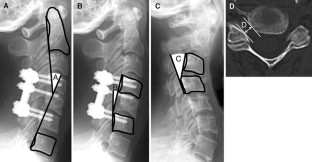

Though a possible cause of late neurological deficits after posterior cervical reconstruction surgery was reported to be an iatrogenic foraminal stenosis caused not by implant malposition but probably by posterior shift of the lateral mass induced by tightening screws and plates, its clinical features and pathomechanisms remain unclear. The aim of this retrospective clinical review was to investigate the clinical features of these neurological complications and to analyze the pathomechanisms by reviewing pre- and post-operative imaging studies. Among 227 patients who underwent cervical stabilization using cervical pedicle screws (CPSs), six patients who underwent correction of cervical kyphosis showed postoperative late neurological complications without any malposition of CPS (ND group). The clinical courses of the patients with deficits were reviewed from the medical records. Radiographic assessment of the sagittal alignment was conducted using lateral radiographs. The diameter of the neural foramen was measured on preoperative CT images. These results were compared with the other 14 patients who underwent correction of cervical kyphosis without late postoperative neurological complications (non-ND group). The six patients in the ND group showed no deficits in the immediate postoperative periods, but unilateral muscle weakness of the deltoid and biceps brachii occurred at 2.8 days postoperatively on average. Preoperative sagittal alignment of fusion area showed significant kyphosis in the ND group. The average of kyphosis correction in the ND was 17.6° per fused segment (range 9.7°–35.0°), and 4.5° (range 1.3°–10.0°) in the non-ND group. A statistically significant difference was observed in the degree of preoperative kyphosis and the correction angles at C4–5 between the two groups. The diameter of the C4–5 foramen on the side of deficits was significantly smaller than that of the opposite side in the ND group. Late postoperative neurological complications after correction of cervical kyphosis were highly associated with a large amount of kyphosis correction, which may lead foraminal stenosis and enhance posterior drift of the spinal cord. These factors may lead to both compression and traction of the nerves, which eventually cause late neurological deficits. To avoid such complications, excessive kyphosis correction should not be performed during posterior surgery to avoid significant posterior shift of the spinal cord and prophylactic foraminotomies are recommended if narrow neuroforamina were evident on preoperative CT images. Regardless of revision decompression or observation, the majority of this late neurological complication showed complete recovery over time.

Fig. 2